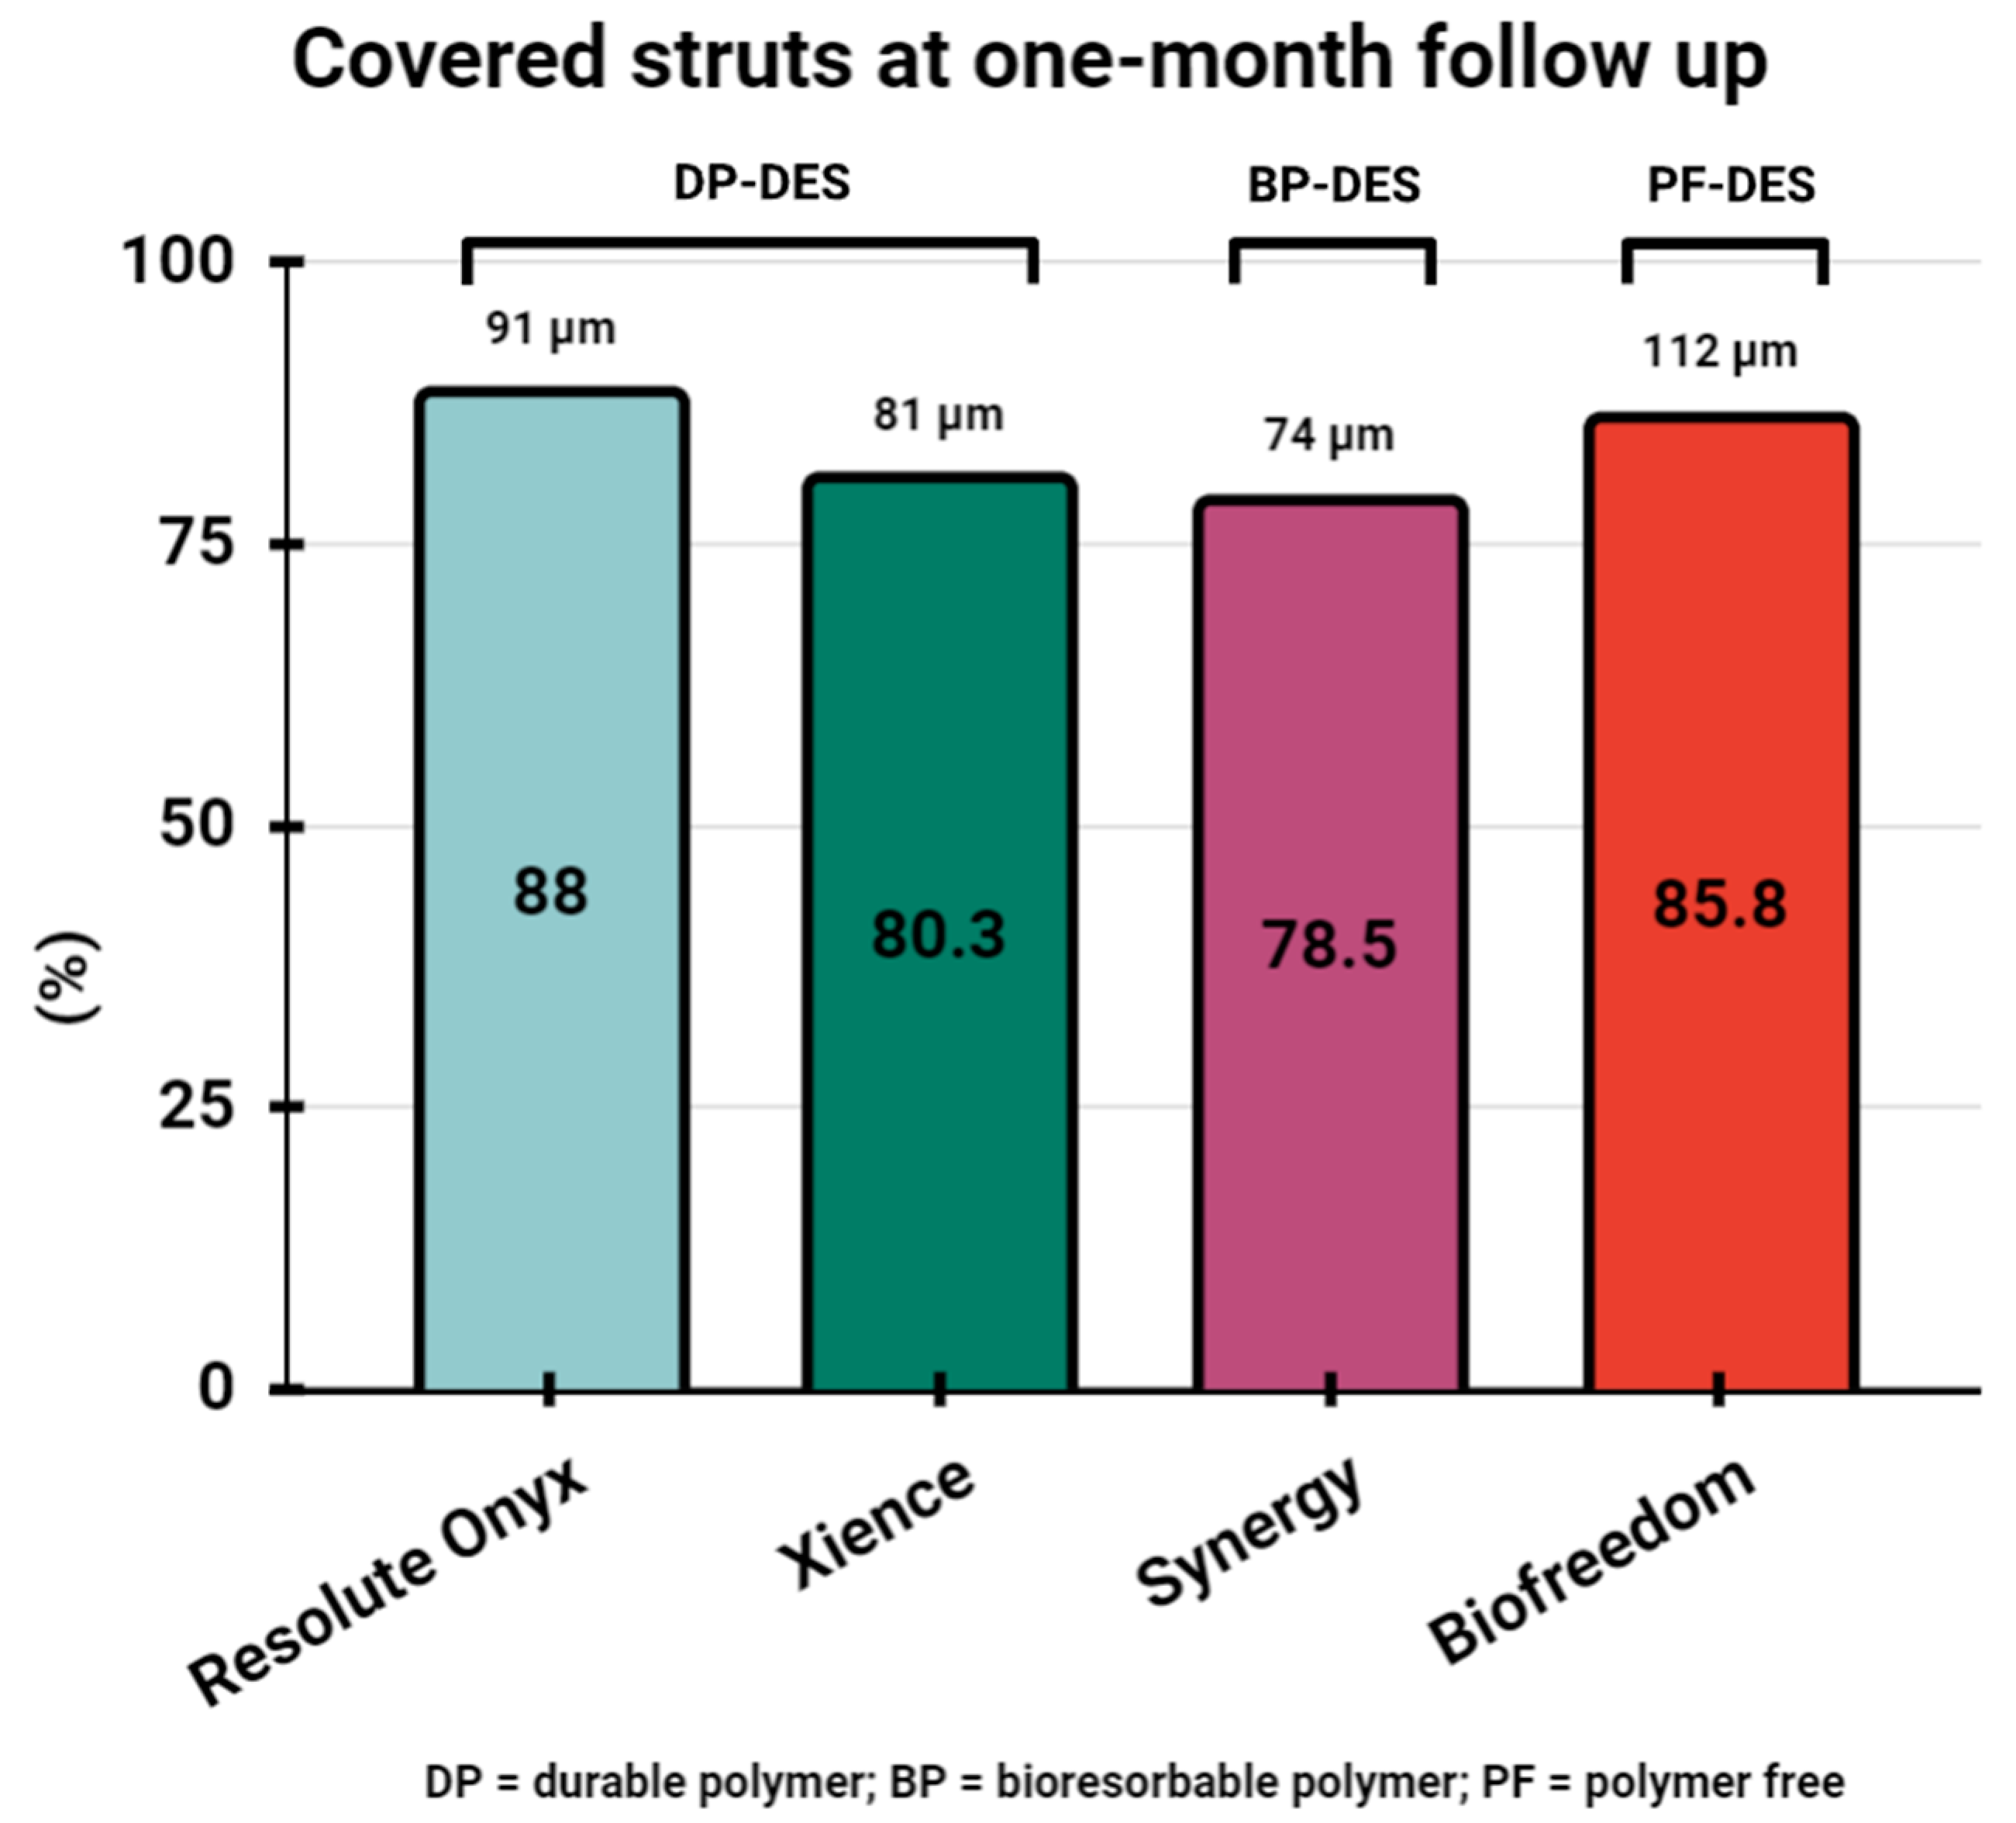

5. Assessment of Stent Healing by OCT One Month following PCI and Safety of One-Month DAPT